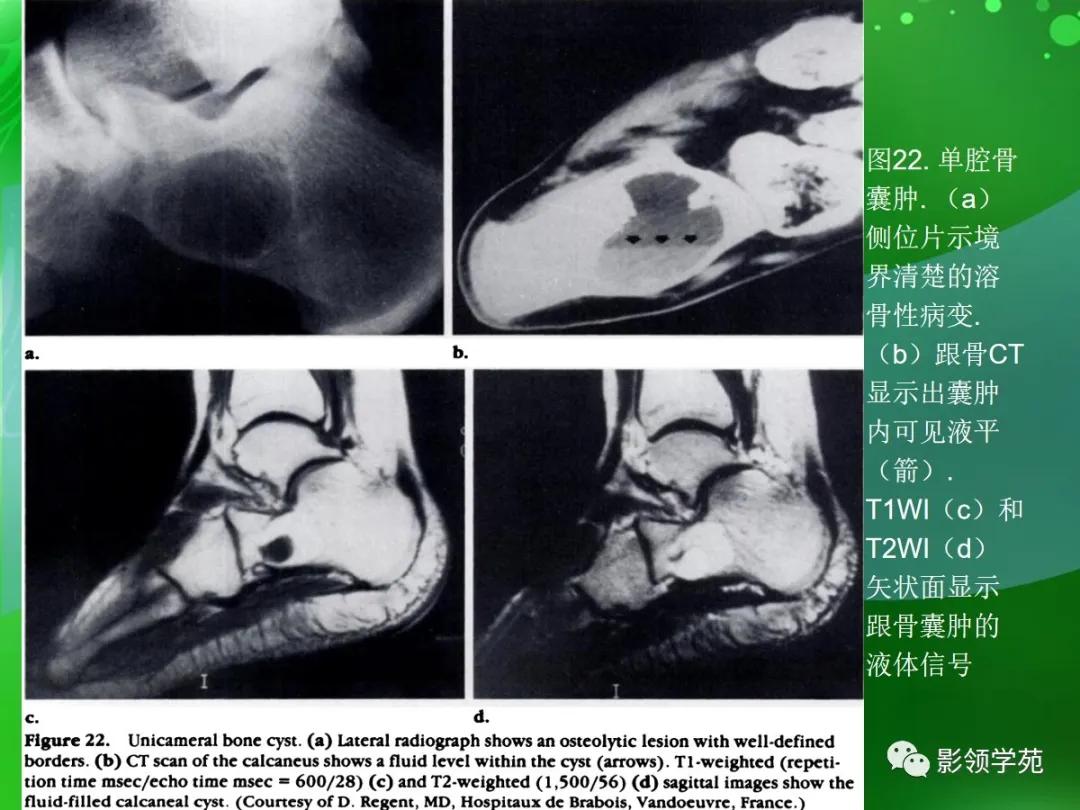

单腔骨囊肿:

约4%的单腔骨囊肿发生在跟骨,是足部最常见部位,占全身发生部位的第3位,80%发生于3~14岁患者,男女比例3:1,可有局部压痛和肿胀。

囊肿内包含清亮、黄色液体,通常抽空后,内附一薄层纤维膜。

影像上, 囊肿通常位于跟骨颈的基部,边界清楚,有薄的硬化边缘,囊 肿的前缘通常平直且呈垂直改变,后缘呈典型的曲线,平行跟骨后部骨小梁 (图22a);CT和MR均能证实囊肿内液体成分,有时可见液平(图22b-22d)。

囊肿可在其病变处发生病理性骨折后或在身体停止生长后自愈 ;囊肿内注射甲基强的松龙的治疗与手术一样有效。